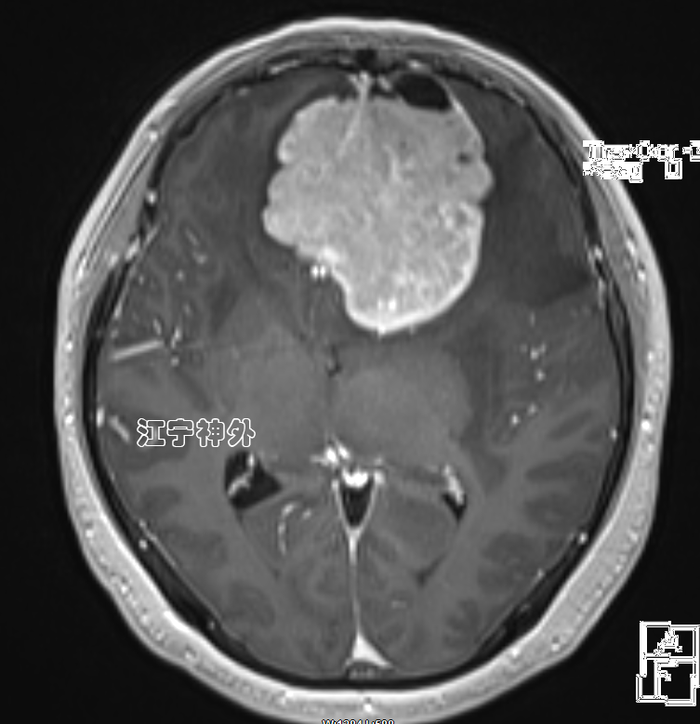

术后一周复查磁共振,显示肿瘤完全切除,脑组织水肿仍比较明显,继续用药。术后两周拆线出院,切口愈合良好,无任何并发症。术后病理提示脑膜瘤。